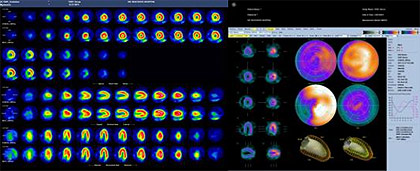

負荷心筋血流シンチ

腎レノグラム